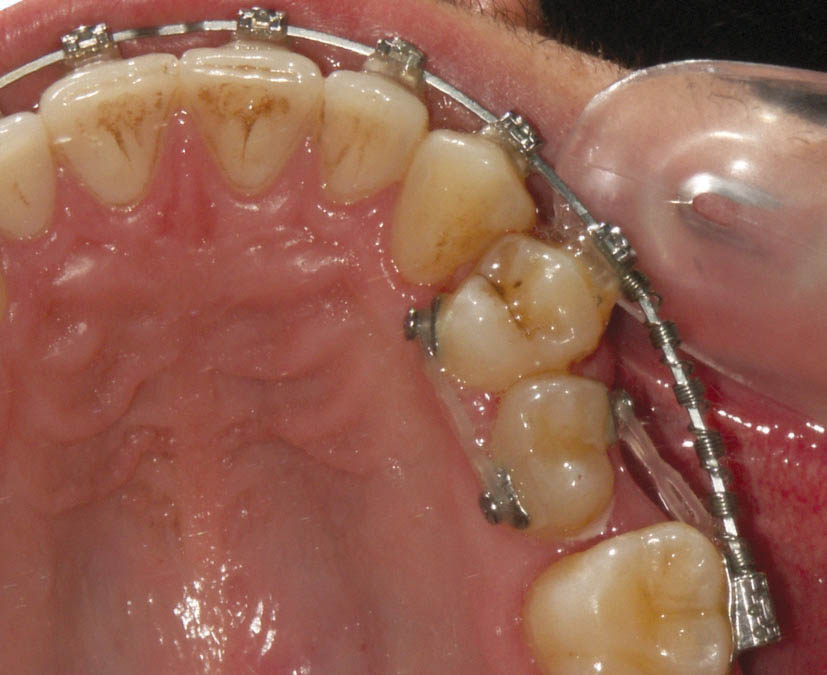

همانطور که دیدید یکی از عوارض چین الاستیک ایجاد چرخش در دندانها است. در شکل 162-1 میبینید که باکال پرمولر دوم به سمت مزیال چرخش دارد، لذا قطعهای از چین الاستیک را از باکال این دندان به مولر اول و از پالاتال به پرمولر اول انداختهایم تا با ایجاد چرخش در پرمولر باعث اصلاح موقعیت آن گردد (شکل 163-1).

در سمت پالاتال دندانها میتوانید از دکمه (صفحه 103) به جای براکت استفاده نمایید.

شکل 162-1: ایجاد چرخش در دندان به کمک Chain Elastic

شکل 163-1: دو ماه بعد تا حدود زیادی چرخش پرمولر دوم درست شده است.